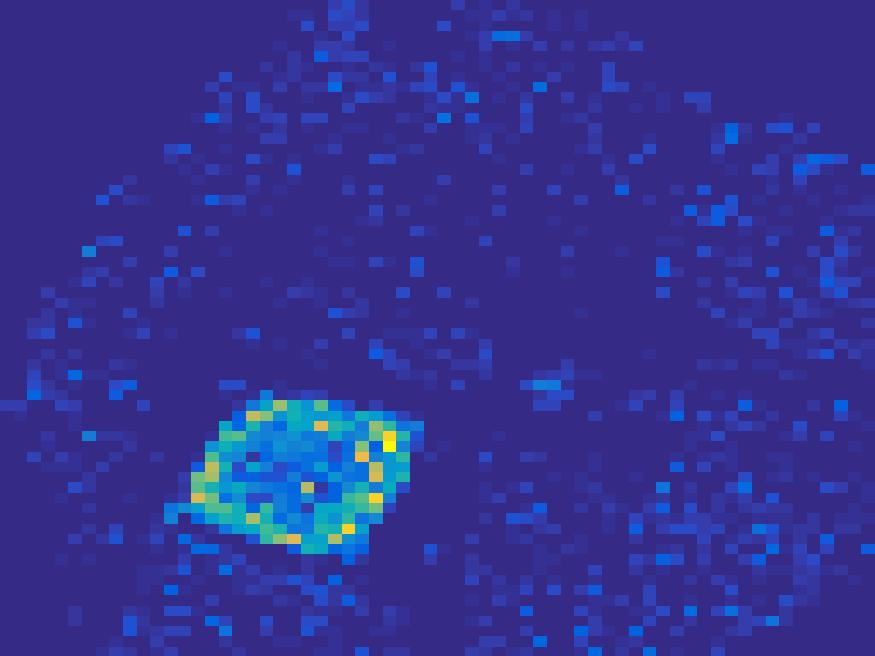

The second numerical experiment is performed on a synthetic image simulating rat’s abdomen, where the bright region represents the heart of a rat. We use the TAC in Figure 2 to simulate the dynamic images.

For the simulated images of rat’s abdomen, the same procedure is applied to generate projection data. Also, noise was added to the sinogram. Figure 5 compares the frames reconstructed by different methods. Clearly, the traditional FBP method and least square method cannot reconstruct the dynamic images with very few projections, however the proposed method reconstructs the images quite accurately. Figure 6 illustrates the comparison of the true TACs and those reconstructed by the proposed method. We can see that they are quite accurate and present small errors.